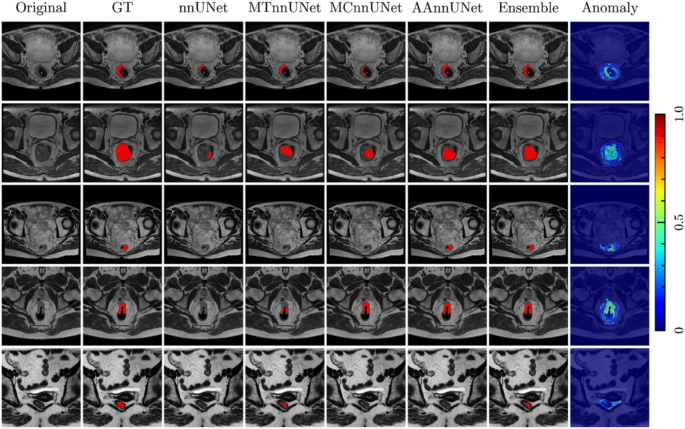

MTnnUNet, MCnnUNet and AAnnUNet (Fully-Supervision)

From Table 4, S6 and Fig. 4a, MTnnUNet and AAnnUNet significantly outperformed both nnUNet and MCnnUNet. Even though MCnnUNet showed the best results in the internal validation (Table S7), it exhibited the lowest aDSC and aHD in the external test. This may be due to MCnnUNet’s reliance on accurate anatomical inputs. It was trained with ground truth anatomical masks but used AI-generated masks (rectum and mesorectum) during inference, introducing inconsistencies that likely contributed to the performance drop on the external test. Unlike MCnnUNet, MTnnUNet uses anatomical knowledge only during training. Although AAnnUNet—fusing anomaly maps that highlight tumoral regions—also relied on the quality of rectum and mesorectum masks, it slightly outperformed MTnnUNet in terms of aDSC. Unlike MCnnUNet, which directly incorporated anatomical masks as input channels, AAnnUNet utilized anomaly maps derived from healthy distributions. We also introduced a union ensemble combining MTnnUNet and AAnnUNet, which improved aDSC by 3%. However, it did not reduce HD. Figure 5 shows that AAnnUNet effectively segmented both small and large tumors, demonstrating the benefit of anomaly fusion. Furthermore, the Grad-CAM saliency map in Fig. S2 indicates that AAnnUNet more effectively captures tumoral features. However, its performance declined when anomaly maps were suboptimal, as seen in the last row. In some cases, all models failed to detect the tumor, though high anomaly map intensities—illustrated in Fig. 6—still indicated potential abnormalities.

The visualization of the segmentation performance of nnUNet, MTnnUNet, MCnnUNet, AAnnUNet, and Ensemble using T2WI, supervised setting. Each row is a different sample from the external test set. The columns from left to right are original T2WI, ground truth, tumor prediction masks from nnUNet, MTnnUNet, MCnnUNet, AAnnUNet, and Ensemble. Colorbar: Shows pixel-wise reconstruction error; higher values indicate greater differences and potential anomalies.

Mixed-supervision, using manually annotated tumors and AI-generated rectum and mesorectum masks, was applied during training on cohort 2, which included 141 cases from a single center for nnUNet, MTnnUNet, MCnnUNet, and AAnnUNet. In the internal validation set, MTnnUNet achieved the best performance, while AAnnUNet performed best on the external test. Unlike the fully supervised setting, MCnnUNet showed improved aDSC and aHD on the external test. This may be attributed to the consistent use of AI-generated rectum and mesorectum masks during both training and inference, leading to more stable performance across datasets (Table 5, Tables S8, S9, Fig. 4b).

In both fully- and mixed-supervision, MTnnUNet outperformed the baseline nnUNet. MCnnUNet showed improvement only in mixed-supervision. Notably, incorporating anomaly maps enhanced tumor localization accuracy across both settings. As illustrated in the first row of Fig. S3, while nnUNet misclassified part of the bladder as tumor due to similar intensities, MTnnUNet, MCnnUNet, and AAnnUNet—fusing anatomical masks or anomaly maps—correctly identified the tumor regions.